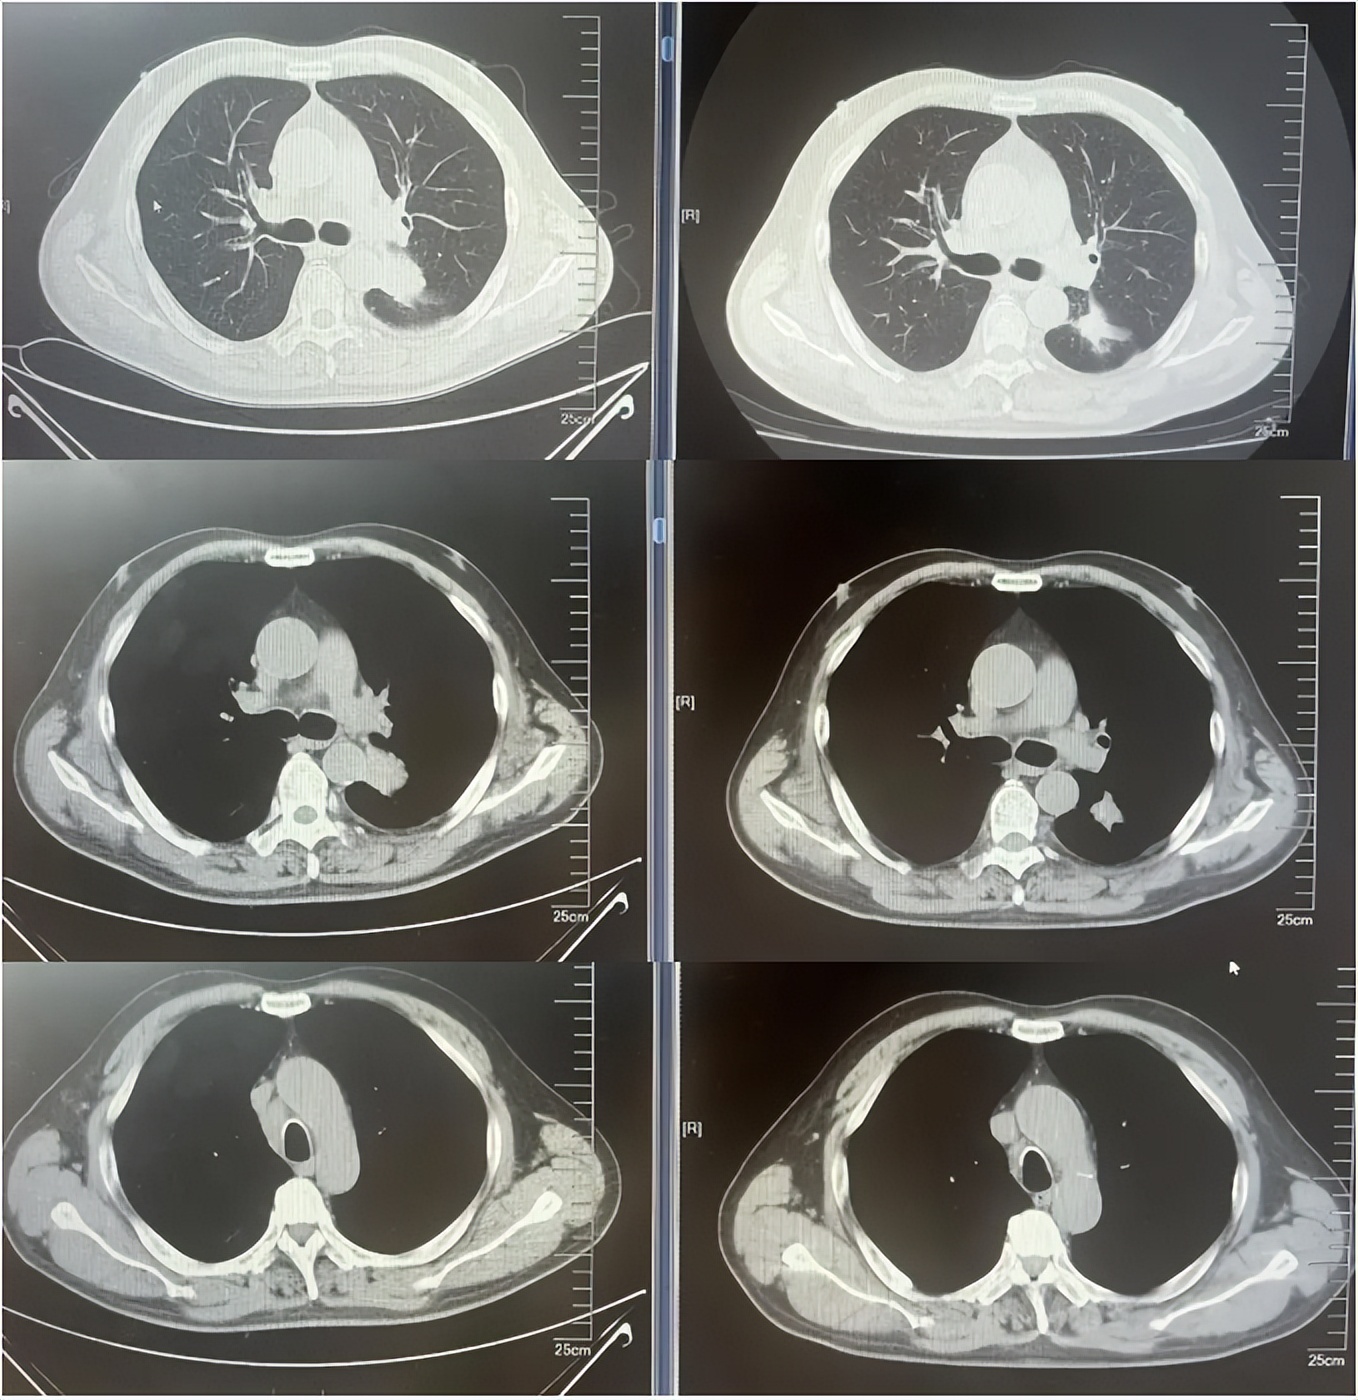

病例1:患者男,68岁。2024年6月以“胸闷气短1个月”为主诉于当地医院检查治疗。查CT提示左肺下叶肿物,纵隔、双肺门多发肿大淋巴结,左侧胸腔积液,左侧胸膜增厚。于当地医院行胸水穿刺引流查癌细胞提示肺腺癌。临床分期:cT2aN3M1a IVA期。患者于当地医院行血液基因检测未见敏感突变,使用AP方案化疗后病情进展。2025-1入我院后行肺穿刺活检,病例提示腺癌。行基因检测提示:ERBB2突变(丰度3.5%)。行德曲妥珠单抗(T-DXd)治疗至今。最佳疗效PR,目前持续有效中,PFS已超过7个月。患者使用德曲妥珠单抗期间出现II级恶心呕吐,经对症治疗可缓解。

德曲妥珠单抗治疗4周期(2025.5)疗效对比

德曲妥珠单抗治疗6周期(2025.7)疗效对比